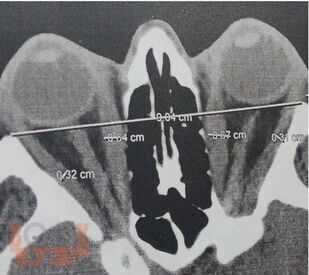

В учебном пособии представлены современные взгляды на этиологию и патогенез повреждения экстраокулярных мышц и ретробульбальной клетчатки при эндокринной офтальмопатии. Большое внимание уделено современным методам диагностики пациентов с данным заболеванием. Подробно рассмотрены современные классификации активности и степени тяжести эндокринной офтальмопатии. С современных позиций изложены основные подходы к лечению данных пациентов.